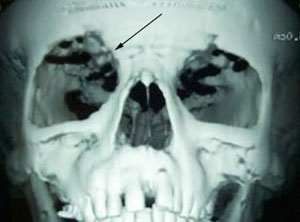

- Specific skeletal abnormalities such as tibial dysplasia (bowing of shin bone) or abnormality of the orbit